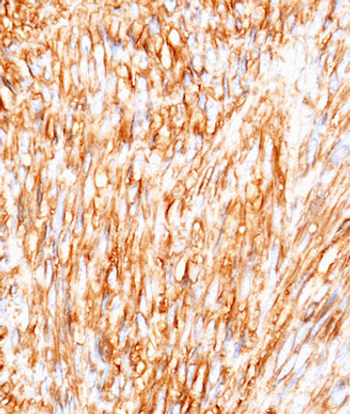

Results of a small study indicate that patients with gastrointestinal stromal tumors had increased activity of Src, but unlike in other tumors, it may be associated with longer overall survival.